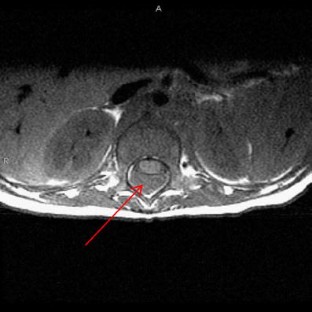

We present a case of a child born with a birthmark over the lumbar spine, which harbored a pinhole-sized opening. At 6 months of age the child presented with fever of unknown origin. Subsequent lower extremity pain resulted in imaging studies that revealed a spinal mass with extension into the posterior mediastinum. At operation, the child was found to have an infected dermal sinus tract.

Fig. 1